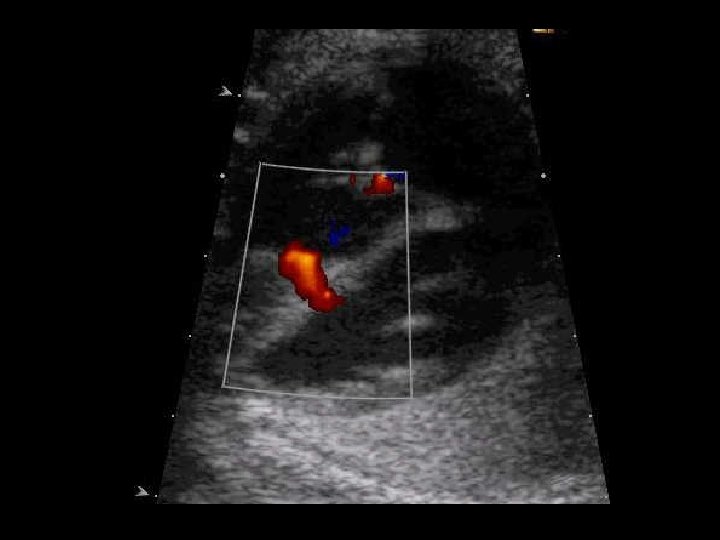

Clínica y diagnóstico o o El soplo puede ser resultado de una CIV o de insuficiencia mitral, ambas condiciones pueden coexistir. Ecocardiograma (TT o TE): Alta sensibilidad y especificidad, seguro, y rápido.

Clínica y diagnóstico o Métodos de diagnóstico por imágenes n Ventriculografía izquierda n Ecocardiografía n TAC n Resonancia magnética